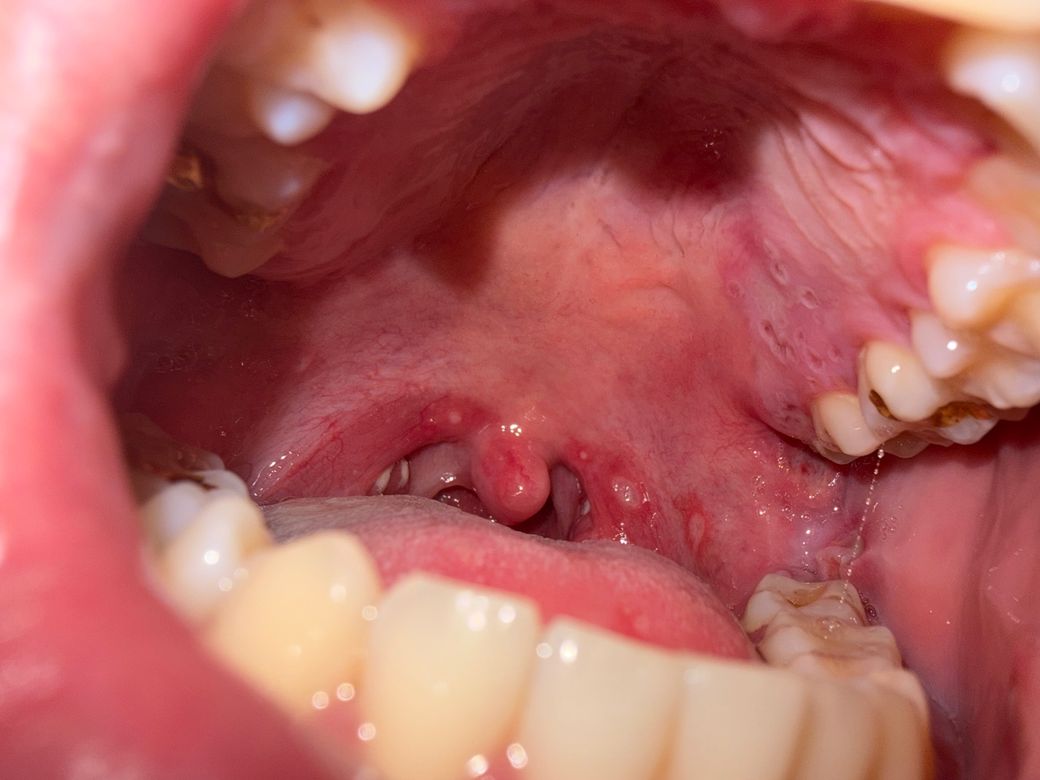

왼쪽이 어제 저녁 두번째 사진이 오늘 아침

• 1번 째 사진

올려주신 사진에서 목 젖 주변이 첫 번째 사진 외 잘 찍히지 않아 호전 여부의 평가가 어렵습니다.

• 사진상으로는 연구개와 구개궁 주변에 국소적인 발적과 작은 궤양성 병변이 보입니다. 전형적인 아프타성 구내염(apthous ulcer) 또는 경미한 바이러스성 인두염에서 흔히 보이는 소견과 유사합니다. 농성 삼출물이나 편도 비대, 뚜렷한 화농성 소견은 두드러지지 않습니다.

사진 비교상 급격한 진행이나 궤양 확대, 화농성 변화는 뚜렷하지 않아 명확한 악화로 보이지는 않습니다. 현재 통증 강도가 비슷하고 발열이 없다면 급성 세균성 편도염 가능성은 낮아 보이며, 이미 항생제를 복용 중이라면 추가적인 항생제 증량이나 변경이 즉시 필요한 상황으로는 보이지 않습니다.